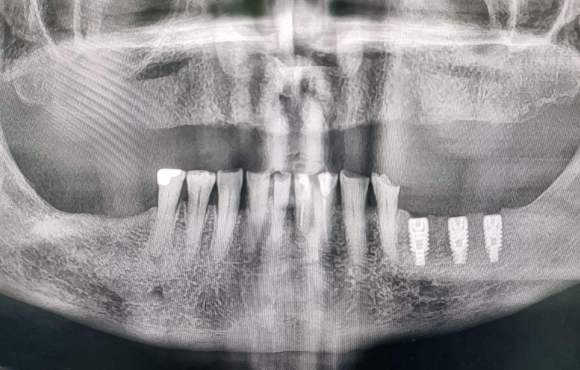

Ci dedichiamo alla chirurgia implantare e alla collocazione di impianti di ultima generazione e dal materiale sofisticato.

Grazie ad uno scrupoloso esame clinico e radiografico valutiamo le condizioni ossee e paradontali necessarie per una osteointegrazione ottimale.